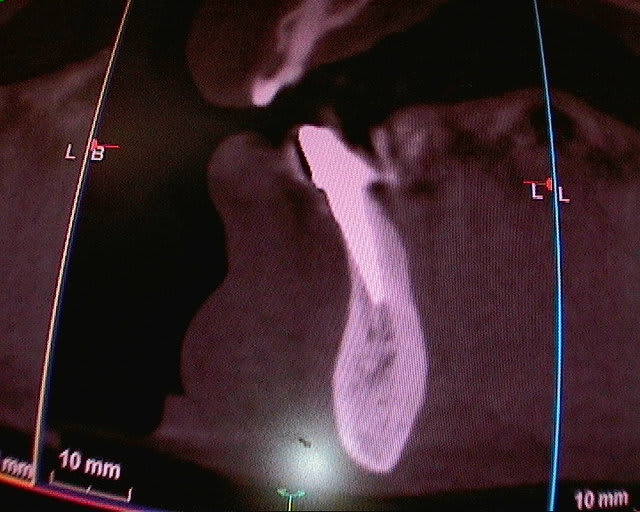

J'ai les scans de contrôle mais à seulement 3 ans (visibles sur d'autres post, mais sur un scan tu ne vois pas 1mm d'os autour d'un col implantaire, d'où le lambeau pour vérifier, mais je ne me vois pas faire un lambeau à tous les contrôles)) et les panos mais sur les panos on ne voit pas l'os vestibulaire.

pour l'imagerie, c'est comme en photo, les capteurs numériques sont de plus en plus performants et "fins"...si ton scan à 3 ans ne montre plus d'os en vestibulaire, tires en les conclusions que tu veux...mais y a fort à parier qu'il n'existe réellement plus...

Le lambeau avec l'os autour des implants était justement suite à un scanner ou je ne voyais pas l'os, et je voulais savoir ce que ça donnait réellement.